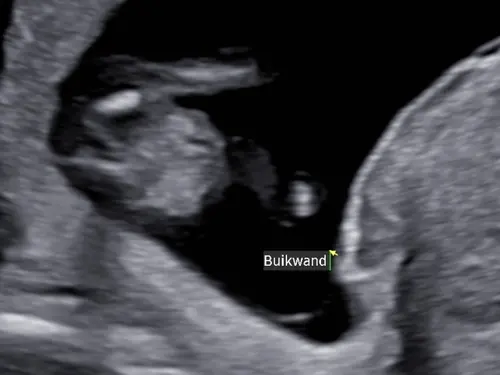

Ik denk dat je dit het beste even bij je verloskundige kan navragen. Ik kan best aardig zelf een echo maken, ben niet opgeleid voor baby's hoor, maar ik vind dit beeld erg lastig zo stilstaand.

Mij lijkt het in ieder geval geen geslacht want dan zou je meer been moeten zien denk ik. Dan eerder de navelstreng maar vind de organen niet duidelijk dan weer dat het om de buik gaat en niet mooi rond genoeg.

Dit is de originele! Kan je hier iets mee ?

Nee sorry maar denk echt dat het sowieso geen geslacht is. Met 13 weken kijken ze daar meestal ook niet naar omdat de kans dat ze het mis hebben erg groot is. En je zou dan maar één been zien en dat is raar.

Dit is een echo vanaf de onderkant bij mijn zoon, toen 13 weken echo. Duidelijk twee benen. Mijn zoon was echt heeeeeeel duidelijk een jongen een week of twee na deze echo maar hier dus eigenlijk zo goed als niet zichtbaar

Zoals ik hem zie is dit een zij aanzicht waarbij het witte een been is, en het pijltje dus ter hoogt van de navel is (ter aanduiding waar de navelstreng uit de buik komt)

was dit met de 13 weken echo? Want dan zou dat het wel verklaren aangezien ze er een pijltje gezet hebben

Jaa is idd met de 13 weken 🥰! Maar normaal zou je dan toch ribbetjes oid z ...

Het is (zover ik zie) in elk geval geen echobeeld van de onderkant, dan zou je 2 benen zien zoals op het beeld wat eerder al gereageerd is in een foto.

Met de 13 weken echo kijken ze ook niet naar geslacht dus daar duidt het pijltje sowieso niet op, al zouden ze het kunnen zien, wat op deze termijn niet betrouwbaar is, zouden ze er geen pijltje bij gezet hebben.